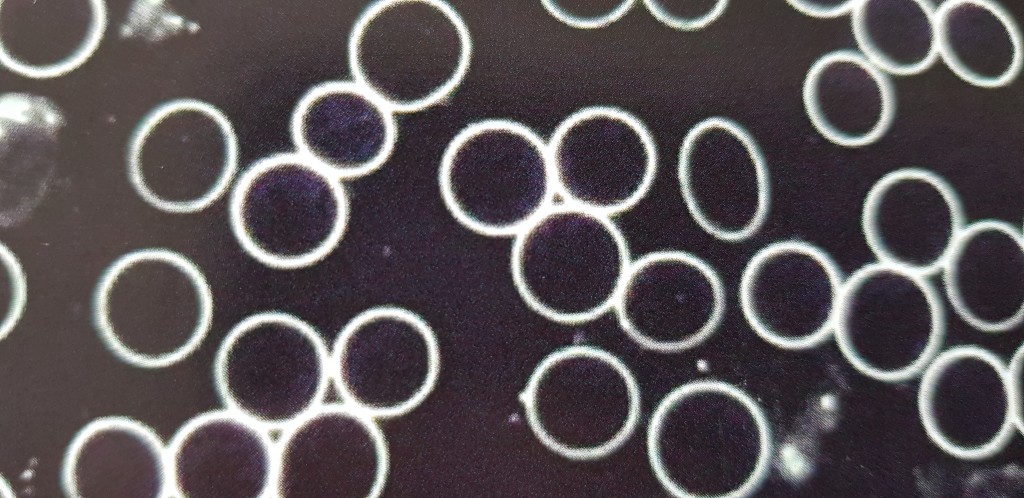

Den Menschen ganzheitlich betrachten, bedeutet, ihn als Einheit aus Seele, Körper und Geist wahrzunehmen. Das Vertrauen des Patienten zu erhalten ist ein Geschenk und gleichzeitig die Verpflichtung zur bestmöglichen Hilfeleistung. Deshalb befasse ich mich seit vielen Jahren intensiv mit den verschiedensten Methoden, die geeignet sind, die Gesundheit und das Wohlbefinden zu fördern. Der Zustand der inneren Ruhe und Entspannung spielt hierbei eine sehr wichtige Rolle. In diesem Zustand ist es auch eher möglich, den Streß im Alltag besser bewältigen zu können und die eigene Leistungsfähigkeit zu steigern. Als weiteren positiven Effekt kann sich die bewußte Wahrnehmung und die persönliche Lebensqualität deutlich verbessern. Leistungen Untersuchung & Behandlung manuelle bioenergetische Behandlungen (incl. Craniomyofasziale Therapie) Augendiagnostik Akupunktur (Nadeln, Laser, Elektroakupunktur, Magnete) Bioresonanzdiagnostik, -therapie Blut-Dunkelfelduntersuchungen nach Prof. Dr. Enderlein Magnetfeldtherapie Medizinisch-therapeutische Hypnosen Autogenes Training, PMR, Meditation Kinesiologie Unterstützung psychosomatischer Prozesse Reiki Bachblütentherapie Auratherapie Therapieschwerpunkte u.a.: Rücken- und Schulter-/Nackenschmerzen, Beinschmerzen Entgiften - entsäuern - ausleiten Verbesserung des Gesundheitszustandes psychosomatische und Bewußtseinsprozesse Streßsymptome wie z.B. auffällige und anhaltende Gereiztheit und Unzufriedenheit, innere Unruhe, Schlafstörungen, "nicht oder nur schwer abschalten können", häufiger das Gefühl haben "irgend etwas stimmt nicht mit mir" oder einfach "nur" die innere Balance vermissen. Streß jeglicher Art ist häufig ein Auslöser für den Beginn von Krankheitsprozessen. Telefonische Terminvereinbarung Montag - Freitag 9:00 -18:00 Uhr Terminvereinbarung Zur Facebook Fansite